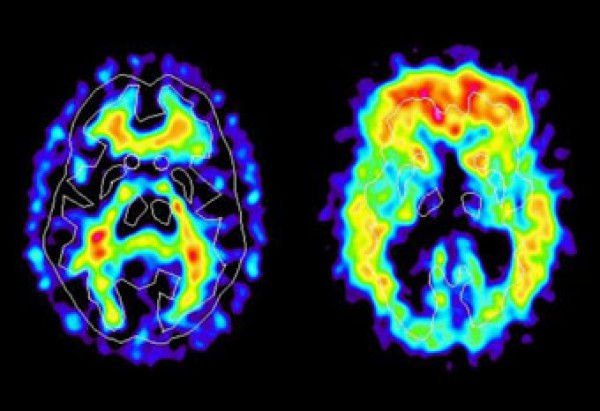

The study tested 52 people, ages 32 to 72, with normal brain function. The test subjects were broken into four equal groups of different backgrounds: those with a father with Alzheimer’s, a mother, both parents and those with no genetic history. The subjects were then given multiple brain scans including Magnetic Resonance Imaging (MRI) and Positron Emission Tomography (PET) scans.

The scans showed that there was a possible increase in Alzheimer’s risk when both parents have the disease. The abnormalities in the brain were the most distinct in those with both parents affected by late-onset Alzheimer’s. Also, the abnormalities were more distinct in those with a mother affected by the disease than those with a father who was affected. All three groups with a hereditary disposition showed a greater loss of gray matter and more plaque in the brain than those who had no family history of Alzheimer’s.